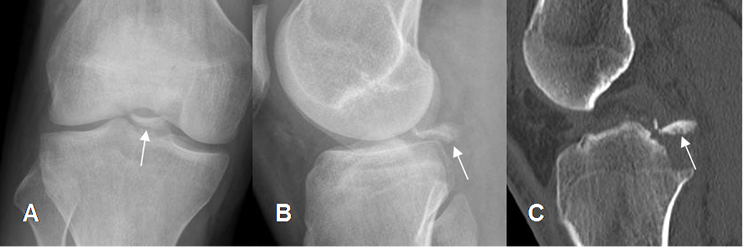

Fig 49. Avulsión de la espina tibial posterior.

A: Rx lateral, B: TAC reconstrucción sagital y C: RM sagital en T2. Avulsión desplazada, de la espina tibial posterior. (Flecha delgada). En la RM se encuentra el LCP íntegro y de aspecto normal. (Flecha gruesa).